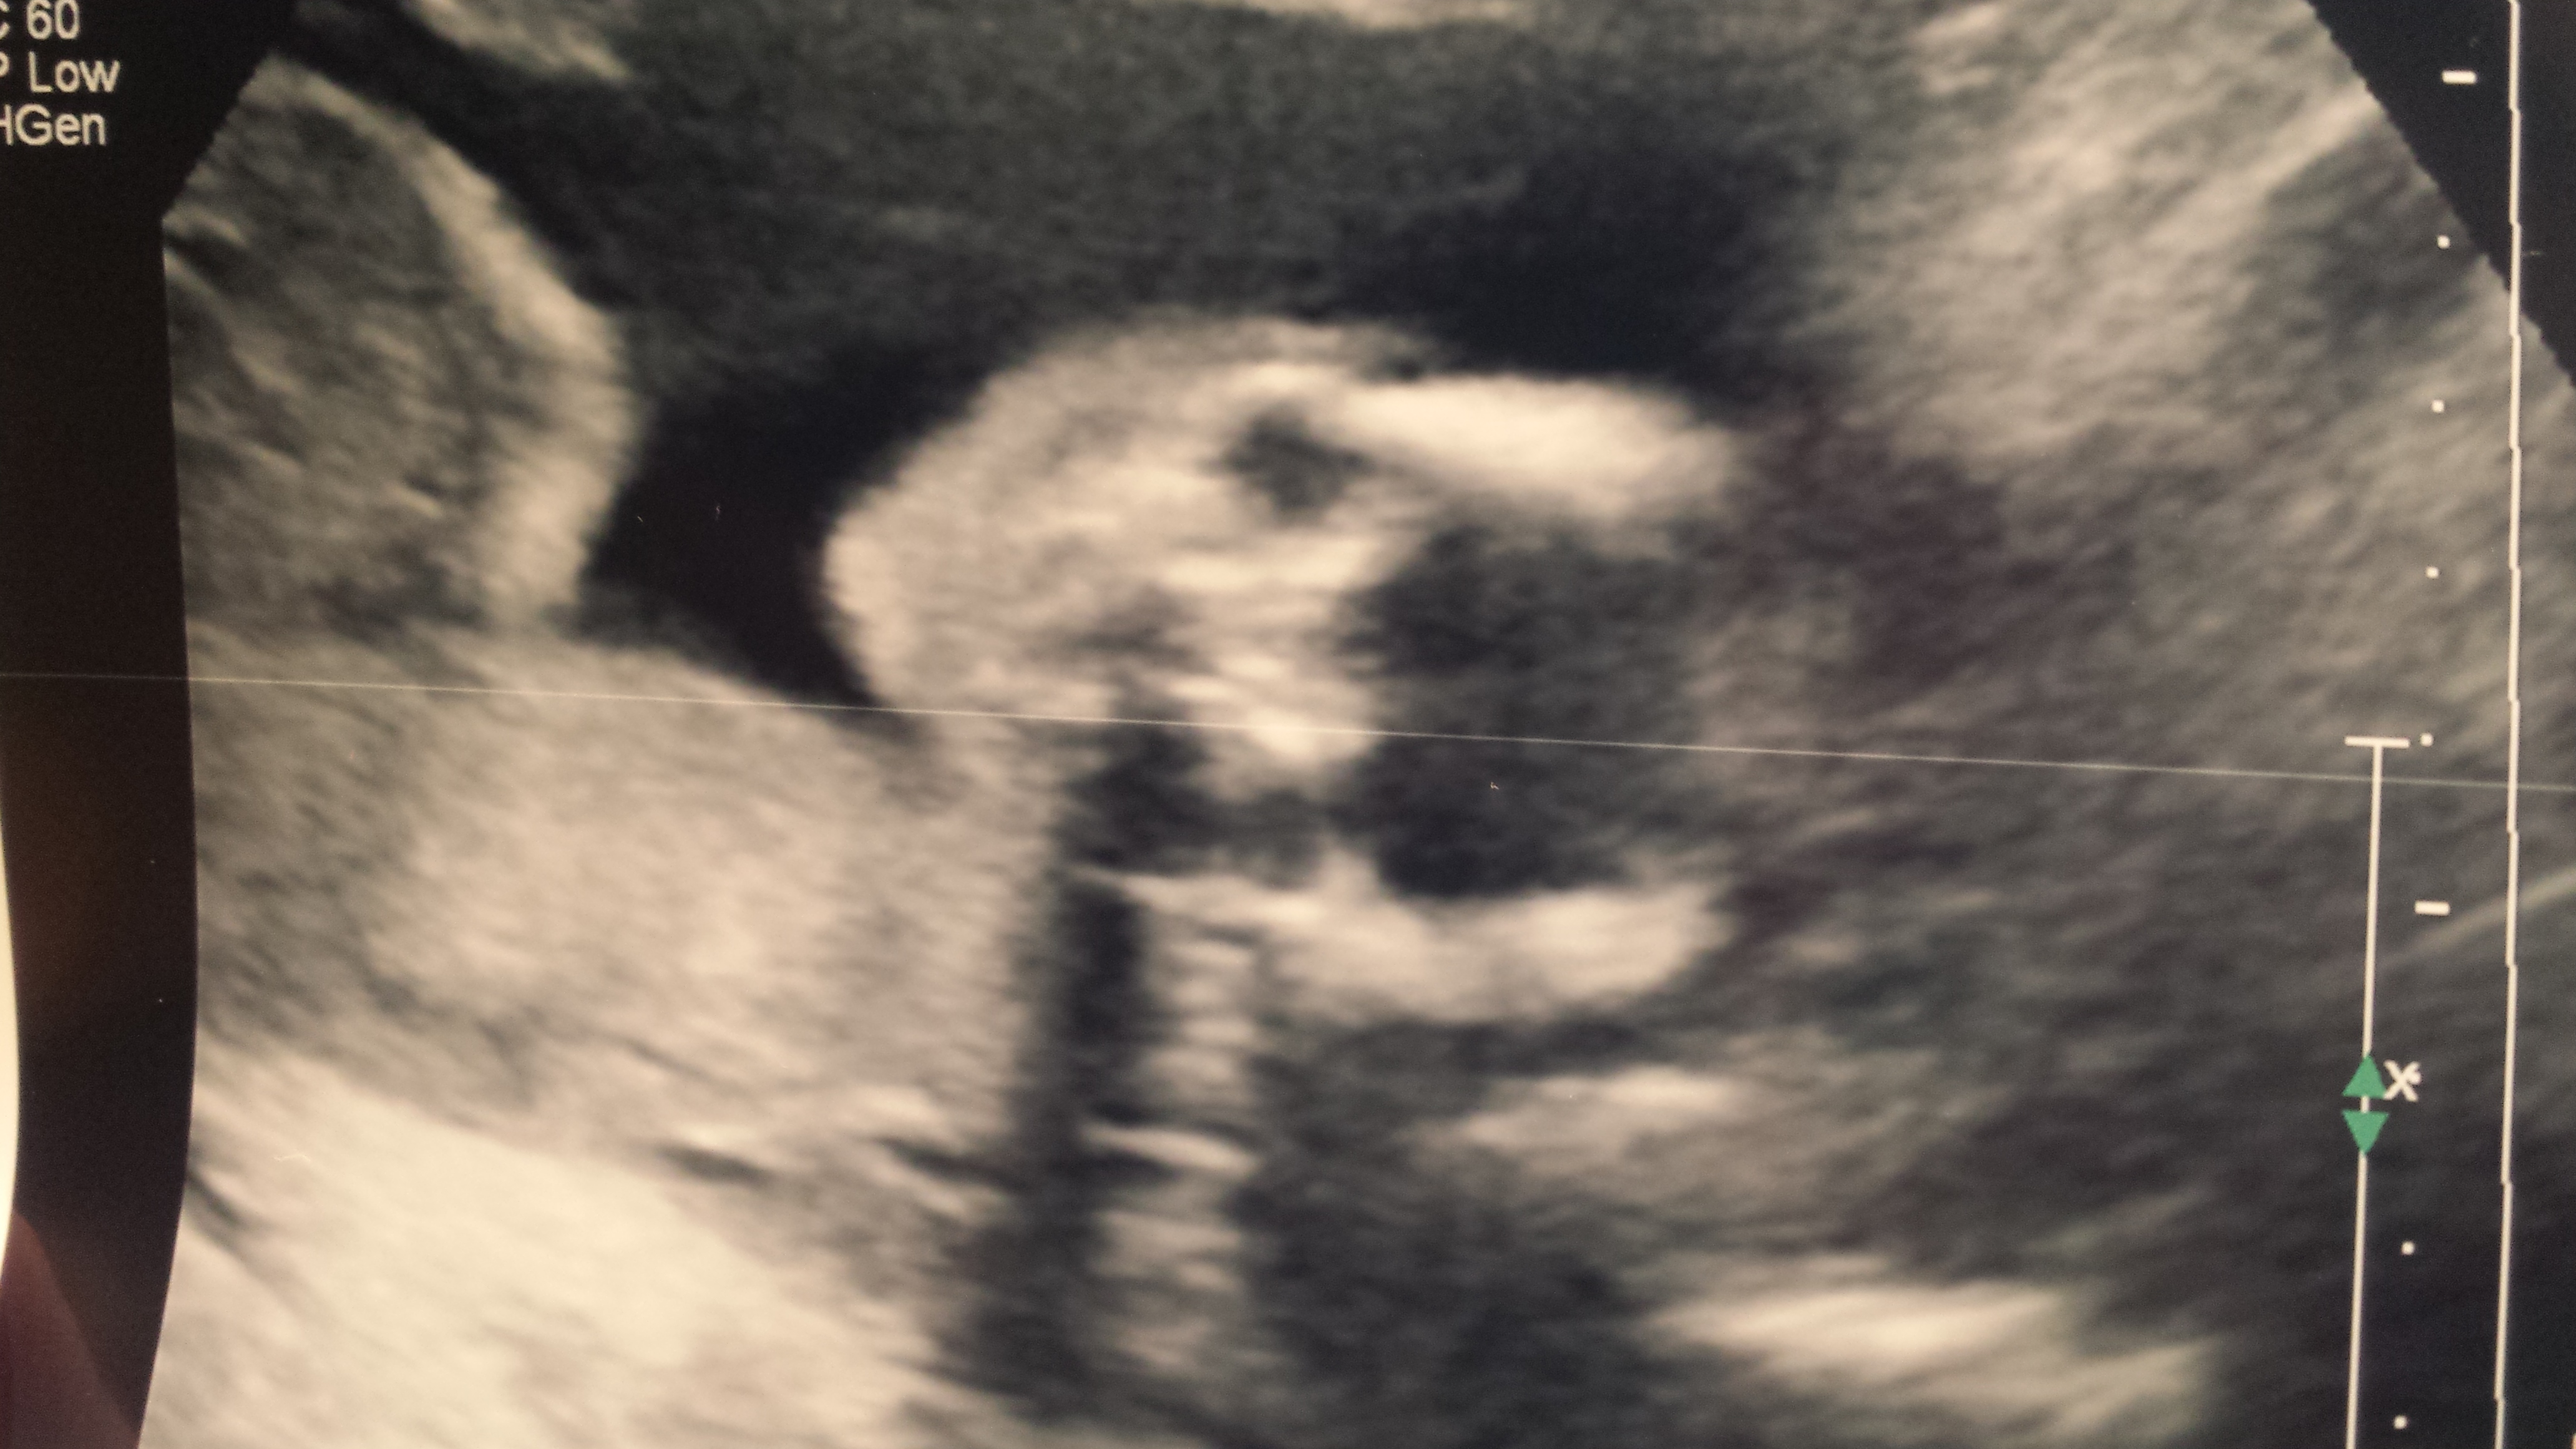

• Healthy boy for us! So exciting!

Aww he looks cute with his hand on his face! Cute pic!